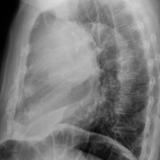

Case 9 Thymoma Lat

Date: 04/04/2010

Views: 3185